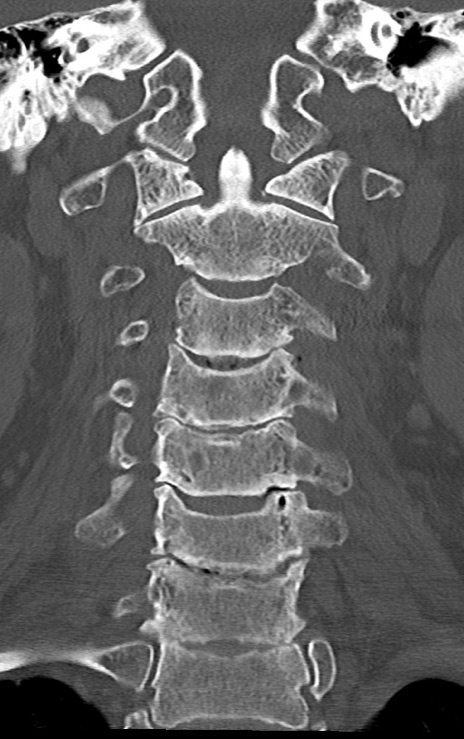

頚椎CT

矢状断像